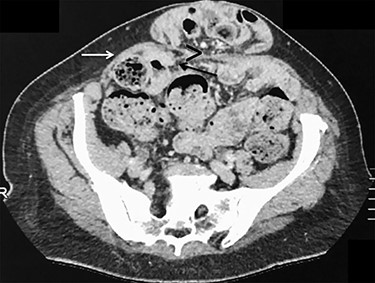

ALH is a peculiar type of interstitial parietal hernia of the anterior abdominal wall subdivided into three types [5] and more commonly identified in man, with a sex ratio difference of 12.5:1. One explanation is that more than a third of females don’t have a defined arcuate line, whereas most males do [6]. ALH rarely causes symptoms, as the hernia orifice is wide and can be easily mistaken as a Spigelian hernia on preoperative imaging that explains the number of cases only being diagnosed at laparoscopy [7]. Similarly, in our case, only the ventral hernia was clinically obvious and the bilateral ALHs were incidentally detected during laparoscopy. This reinforces the superiority of laparoscopy that allows us, alike in groin hernia surgery, to detect and simultaneously repair any coexistent defects [8]. Anecdotally, further re-examination of the preoperative CT-scan could probably reveal ascending protrusion of bowel between the right posterior rectus sheath and rectus muscle (Fig. 6).

Axial view of contrast-enhanced CT scan showing a small opening (>) with ascending protrusion of bowel between the posterior rectus sheath (black arrow) and the rectus muscle (white arrow).